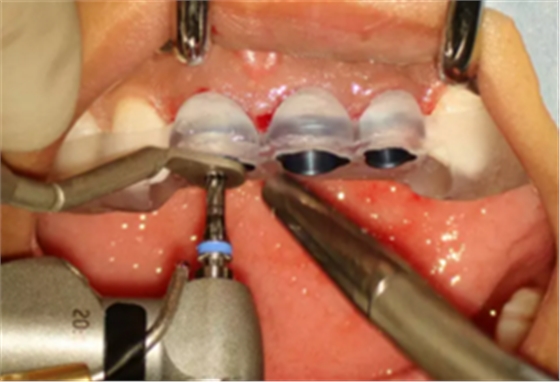

(2)即刻种植、即刻临时修复。术中不翻瓣微创拔除牙根,牙槽 窝骨壁完整。在多级导板辅助下完成种植窝洞制备,植入Bego柱形种植 体,型号分别为:上颌右侧中切牙位点4.1mm×15mm、上颌左侧中切牙 位点?3.75mm×15mm、上颌左侧侧切牙位点3.25mm×15mm,扭矩均为 35N·cm。种植体与唇侧骨壁间隙约2mm,植入Bio-Oss®Collagen骨胶 原。戴入桥用钛临时基台,临时冠就位顺利,自凝树脂口内粘接后适当修整 外形,充分磨光,调 至正中 、前伸 和侧方 与对颌牙均无接触。术后 根尖片显示种植体位置、方向良好。

图8 导板辅助下备洞